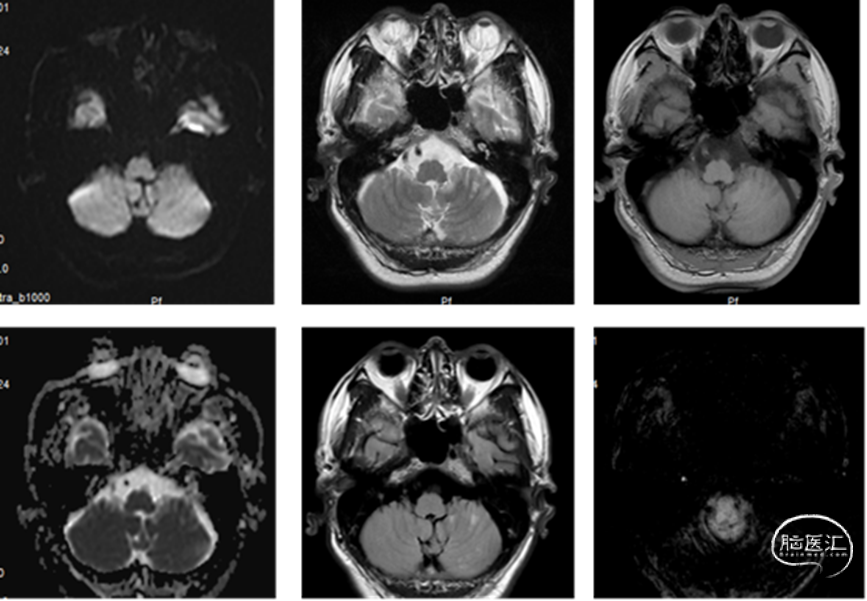

头颅核磁示:双侧小脑、双侧枕叶多发性脑梗死,部分趋于急性期。头颅磁共振MRA提示:双侧椎动脉V4重度狭窄;基底动脉上段轻度狭窄。

术前影像学检查

脑血管造影:主动脉弓+右侧颈总动脉造影。

左侧颈总动脉造影。

左侧锁骨下动脉造影。

右侧锁骨下动脉造影。

术前诊断:

1.脑梗死(右小脑)

2.右侧椎动脉V4段重度狭窄

3.左侧椎动脉重度狭窄

4.左侧小脑后下动脉重度狭窄

5.基底动脉尖段轻度狭窄